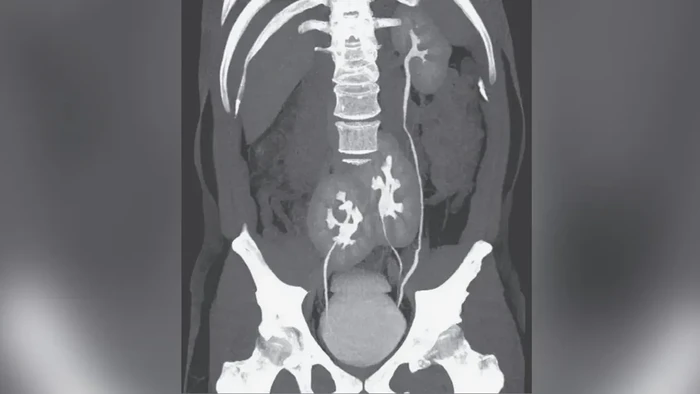

Di luar temuan itu, CT scan juga memperlihatkan kelainan anatomi langka. Pasien memiliki satu ginjal normal di sisi kiri, serta dua ginjal yang menyatu dan terletak di area panggul.

Meski demikian, seluruh ginjal tampak berfungsi normal tanpa menimbulkan keluhan khusus.

Biasanya, setiap ginjal terhubung ke kandung kemih melalui saluran ureter. Pada pasien ini, satu ginjal panggul terhubung langsung ke kandung kemih, sedangkan ureter ginjal panggul lainnya bergabung dengan ureter ginjal kiri sebelum masuk ke kandung kemih.